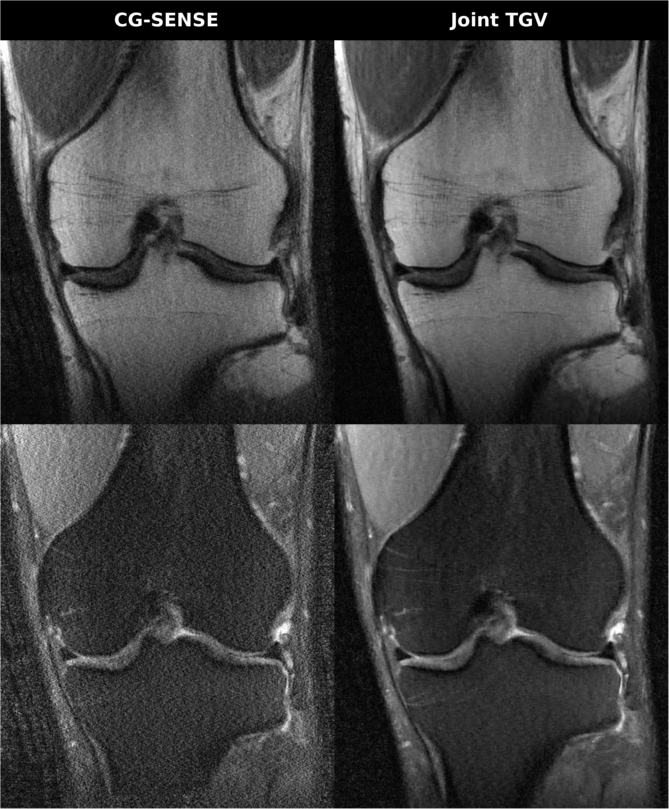

• [46] K. Vunckx, A. Atre, K. Baete, A. Reilhac, C.M. Deroose, K. Van Laere, and J. Nuyts, Evaluation of three MRI-based anatomical priors for quantitative PET brain imaging., IEEE Trans. Med. Imag. 31 (2012), no. 3, 599–612.